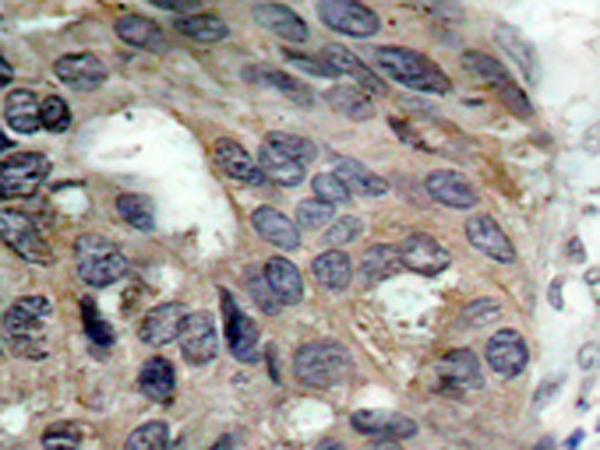

IHC positive control: |

Human breast carcinoma |